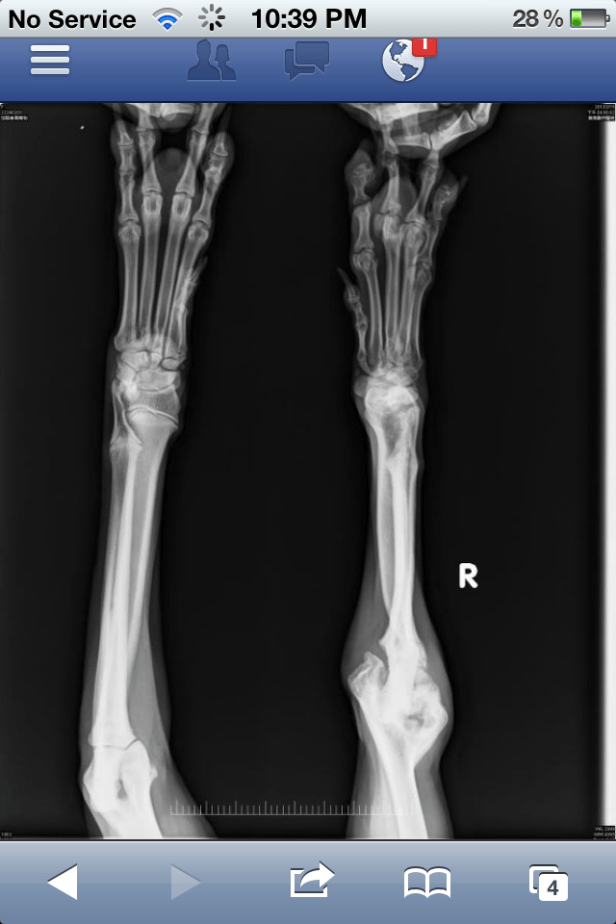

And, if plans go accordingly, her front leg will be fixed.

Unable to move, in October 2011, Nalla was carefully picked up off the street by a TUAPA volunteer. Now, less than five months later, she’s in a happy, safe place. She’s home!